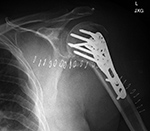

Humerus periarticular locking plate with Vitoss bone graft substitute

Bilateral proximal humerus periarticular locking plates

Periarticular plate

Humerus periarticular locking plate with bone substitute

Right humerus periarticular locking plate

Left humerus periarticular locking plate

57 year-old man with comminuted bilateral proximal humerus fractures. Skin staples are present. There are old, healed rib fractures on the left.